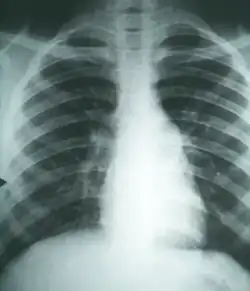

![]() Cambios histopatológicos en un caso de coccidioidomicosis de pulmón, con un nódulo fibrocaseoso grande. | ||